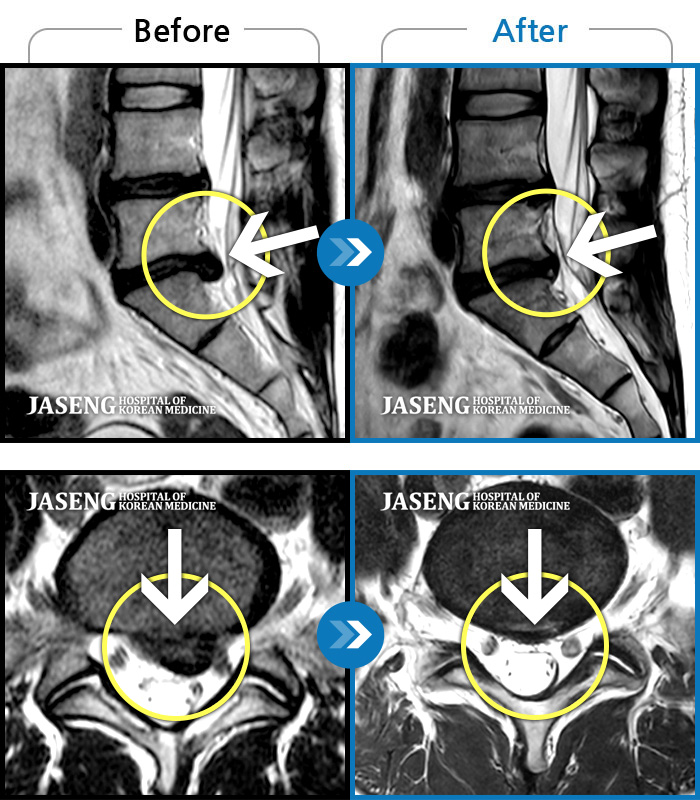

자생 비수술 한방통합치료 후

터진디스크가 흡수된 모습

Before

터진디스크 한방통합치료 전

After

터진디스크 한방통합치료 후

비수술 치료만으로

터진 디스크 흡수

튀어나온 디스크 대비,

터진 디스크 치료 효과 우수

디스크 흘러내린 정도가

심할수록 흡수 가능성 증가

치료 후 장기추적관찰 결과,

환자 90% 이상 치료 만족